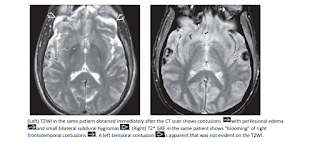

Head Emergency: Diagnostic Imaging (Click on image to magnify). Get link Facebook X Pinterest Email Other Apps - February 07, 2020 Get link Facebook X Pinterest Email Other Apps Comments